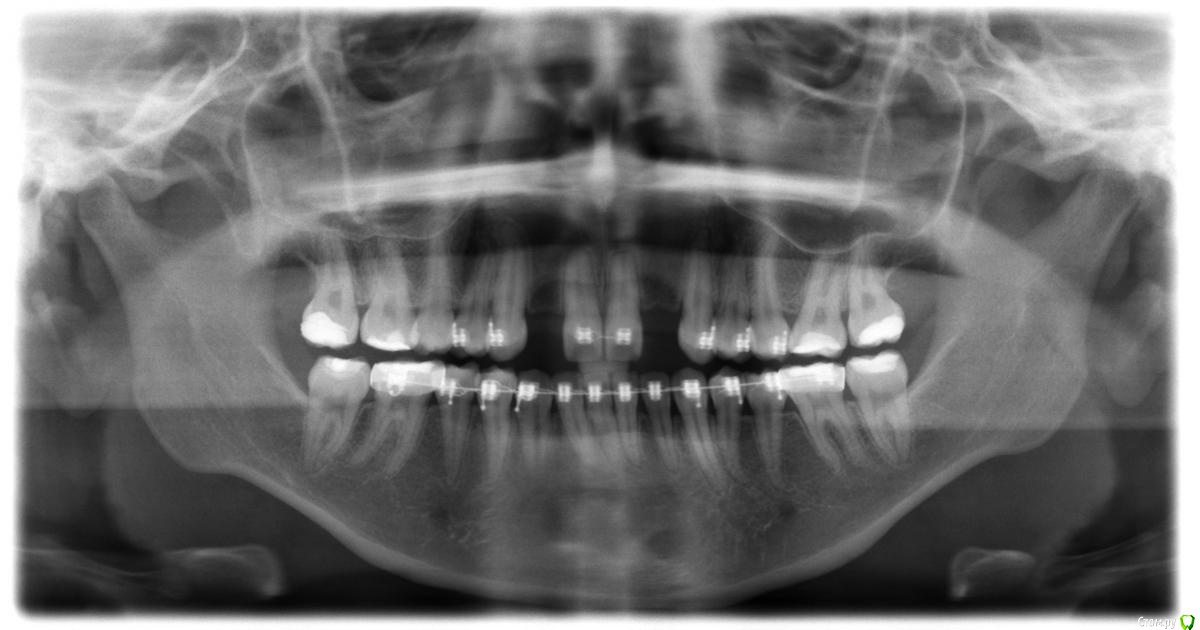

Амина Опубликовано 4 июня, 2016 Автор Поделиться Опубликовано 4 июня, 2016 вот снимок 2016 года Ссылка на комментарий

Амина Опубликовано 4 июня, 2016 Автор Поделиться Опубликовано 4 июня, 2016 Это снимок 2015 года Ссылка на комментарий